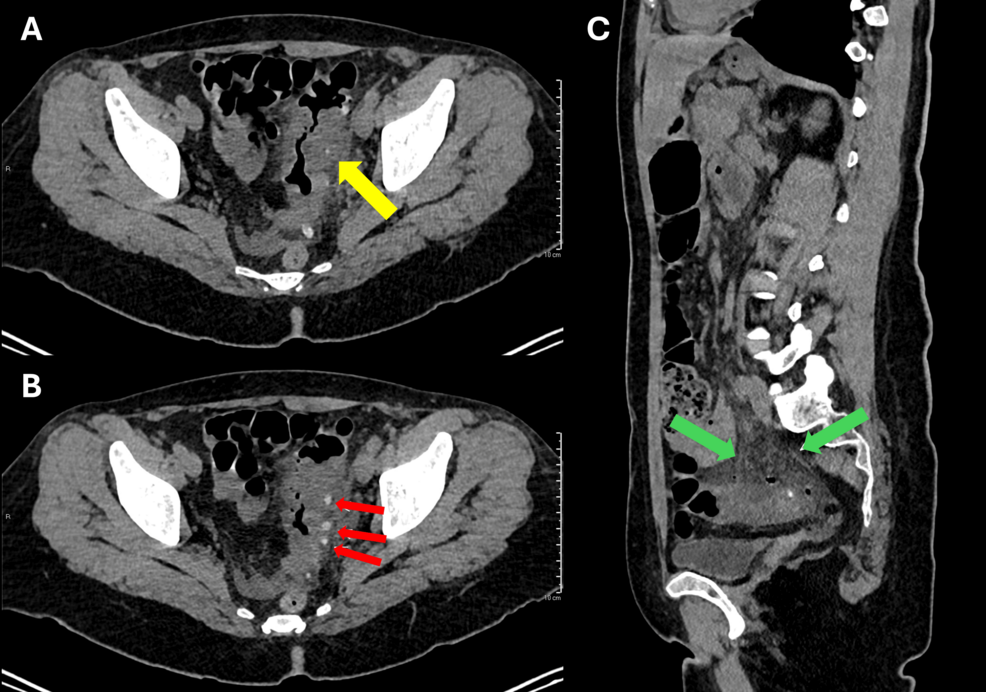

The medical team conducted a thorough evaluation, including a CT scan, which revealed thickening of the sigmoid colon wall and surrounding inflammation consistent with diverticulitis. Laboratory tests confirmed elevated inflammatory markers, further supporting the diagnosis. The patient was treated with intravenous antibiotics and supportive care.